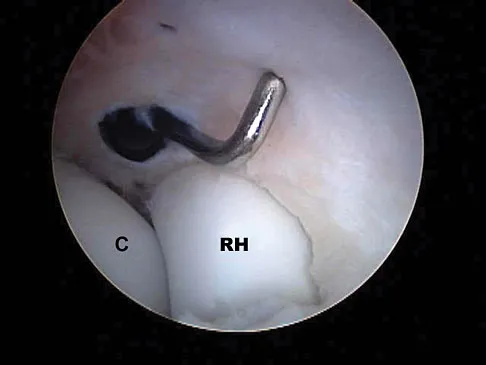

A 40-year-old man has a painful mass on his anterior ankle joint with limited range of motion. A radiograph, MRI scan, a gross specimen, and a hematoxylin/eosin biopsy specimen are shown in Figures 5a through 5d. What is the most likely diagnosis?

Explanation